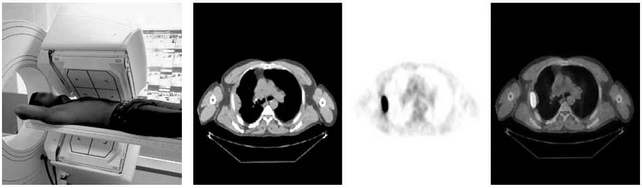

Pozitronová emisná tomografia (PET) - Je najmodernejšou

zobrazovacou metódou nukleárnej medicíny. Pri tomto vyšetrení je do

tela pacienta intravenózne podané rádiofarmakum, čo je špeciálny

farmaceutický prípravok označkovaný vhodnou rádioaktívnou látkou

(rádionuklidom), ktorý sa vychytá vo vyšetrovanom orgáne a umožňuje

jeho zobrazenie.

V onkologickej diagnostike sa z rádiofarmák v súčasnosti

najčastejšie využívá 18FDG (fluorodeoxyglukóza), pomocou ktorej

možno určiť aktivitu (viabilitu) nádoru, podľa toho, do akej miery

sa v ňom glukóza metabolizuje. Tento spôsob metabolického

zobrazenia sa využíva v diferenciálnej diagnostike aktívneho

nádorového tkaniva, pri určení rozsahu nádorového ochorenia,

posúdení účinku protinádorovej liečby, odhalení miesta recidívy

nádorového ochorenia, ale aj pri posúdení gradingu ochorenia alebo

hľadaní primárneho nádoru pri známej metastáze (Makaiová, 2006,

s.29).

Po aplikácii rádiofarmaka sa po niekoľkých sekundách, alebo

minutách pomocou krvného obehu rádiofarmakum dostane až na cielené

miesto, ktorým je najčastejšie nádor. Rádioaktívna látka vysiela z

vyšetrovanej oblasti radioaktívne žiarenie, ktoré dopadá na

detektor PET kamery a následne je elektronicky spracované, pričom

sa vyšetrovaná oblasť zobrazuje na obrazovke počítača (Pavúk, 2003,

s.4).

Najvýznamnejsím prínosom v týchto metódach je fúzia (spojenie)

funkčných a anatomických tomografických metód (napr. PET/CT,

ECT/CT, ECT/ MRI).